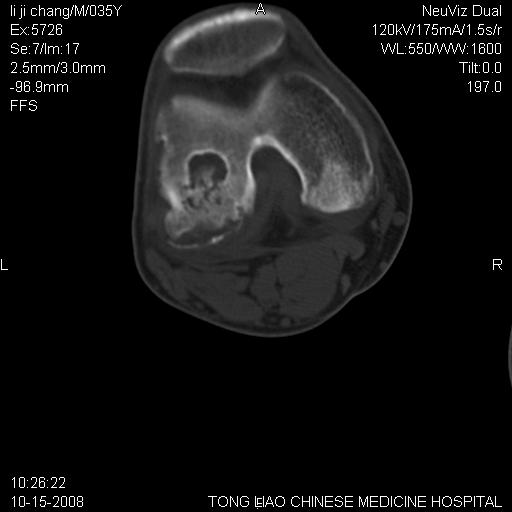

男,35岁,骨科诊断骨性关节炎。继往使用过激素,现股骨头坏死。膝关节病变,请会诊

一元论-----亦考虑为坏死

支持考虑无菌坏死

支持无菌坏死伴退行性骨关节病.

剥脱性骨软骨炎:是一种关节下软骨及软骨下骨缺血性坏死。

支持 无菌性坏死伴退行性骨关节病。